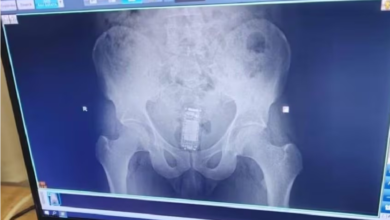

എക്സ്-റേയിലൂടെ കണ്ടെത്തിയത് തടവുപുള്ളിയുടെ ശരീരത്തിനുള്ളിലെ ഫോൺ…തുമ്പായത് ചാർജർ…

സ്വന്തം മലാശയത്തിൽ തന്നെ ഫോൺ ഒളിപ്പിച്ച തടവുകാരനെ പിടികൂടിയിരിക്കുകയാണ് ഗുജറാത്തിൽ ഭാവ്നഗറിൽ. അന്വേഷണോദ്യോഗസ്ഥര് സെല്ലുകൾ പരിശോധിക്കുന്നതിനിടെ ഫോണിന്റെ ചാർജർ കണ്ടെത്തിയതാണ് തുമ്പായത്. ഇതോടെ ജയിലിനകത്ത് മൊബൈല് ഉപയോഗിക്കുന്നുണ്ടെന്ന്…